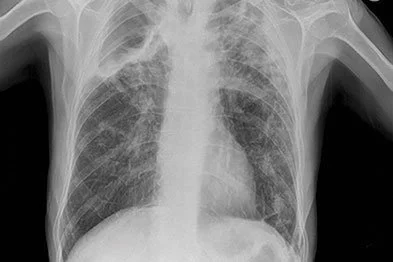

Radiological scans (Chest X-rays, CT scans etc.)

They have a normal radiological scan (Chest X-rays, CT scans etc.).